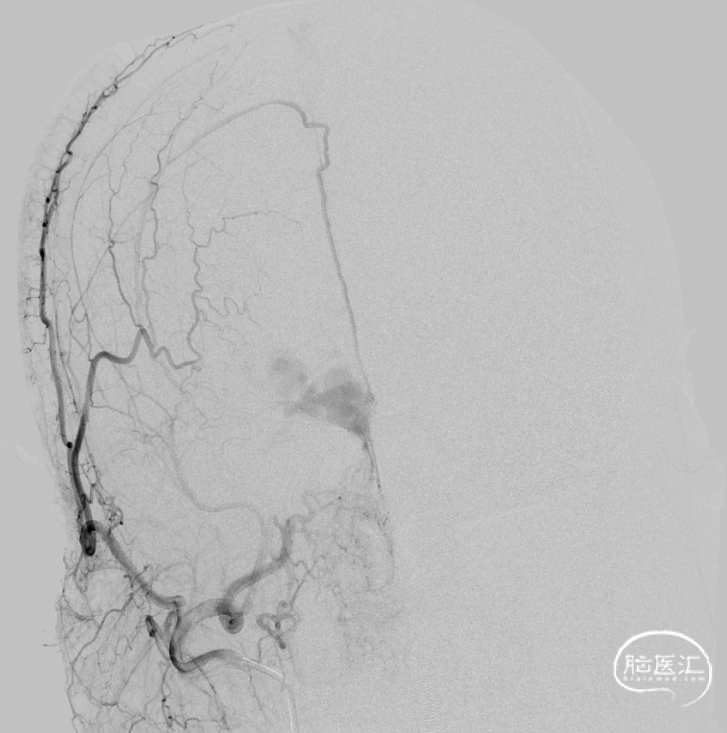

一期治疗

治疗经过